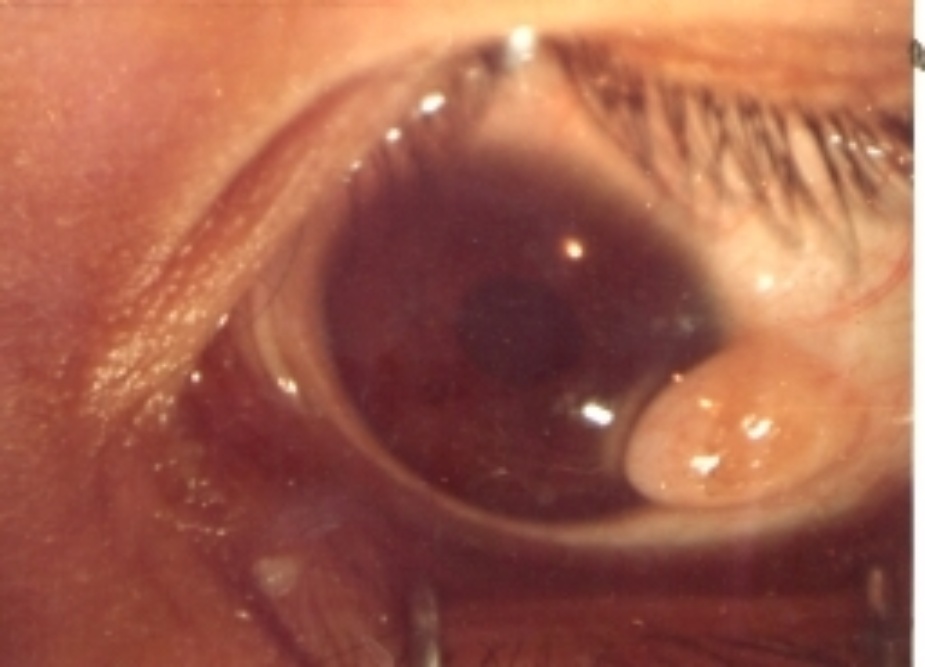

移植片的转归;10例中,术后1个月~1年植片透明愈合1例,半透明4例,混浊3例,植片脱落2例。随访5~8年植片半透明4例,混浊6例(其中植片有新生血管2例,脱落2例包括在内)。视力:10例中,出院时视力较术前提高3行以上或从眼前手动、指数提高到0.1以上者3例,无变化7例;随访4个月~8年视力提高3行以上或从眼前手动、指数提高到0.1以上者3例,无变化6例,有1例植片由透明变成混浊,视力由出院时0.5下降到眼前手动(见附录部分病例彩色图片)。

附 录

鹅角膜板层移植部分病例

第四例